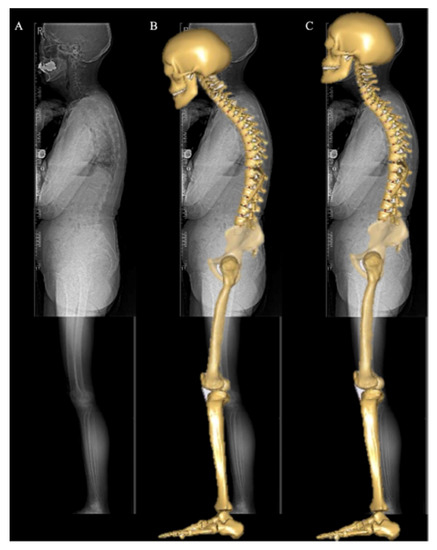

2.2. Image Acquisition and Anatomical Parameters Extraction